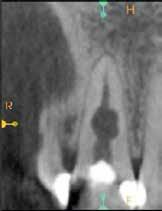

Az elváltozást egy diagnosztikai céllal készített panoráma-röntgenfelvételen észlelték. Az elváltozás kiterjedésének pontos meghatározása, valamint a kezelési terv felállításának és a várható prognózis megítélésének elősegítése érdekében CBCT-felvétel készült (1. a–c ábra). A reszorbtív lézió a fog gyökerének középső harmadában helyezkedett el és a

1. a–c ábra: Kiindulási CBCT-felvétel. Az axiális síkú metszeten jól látható a gyökér falának perforációja (a); Koronális irányú metszet (b), Saggitális irányú metszet